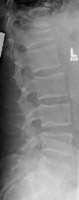

- Click on the image for a larger versionALateral radiograph of the lumbar spine. This shows an osteoporotic compression fracture of the L1 vertebral body.